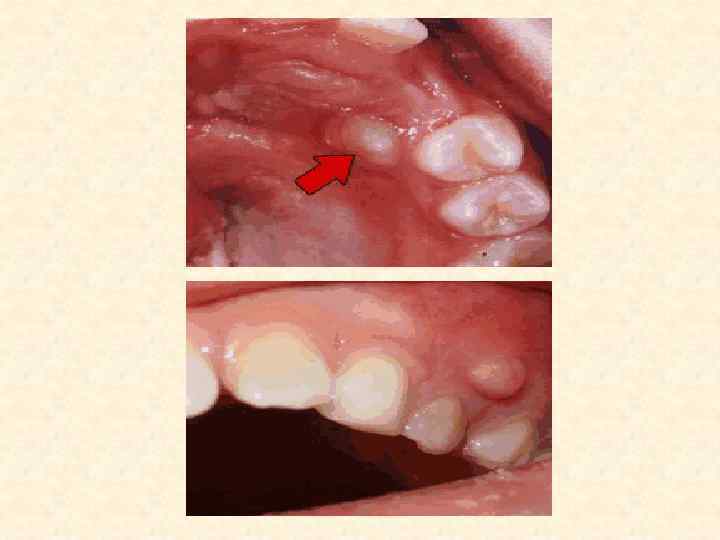

• Слизистая оболочка, покрывающая альвеолярный отросток в области верхушки корня зуба с гранулирующим очагом в периодонте, обычно слегка отечна и гиперемирована, при надавливании пинцетом или зондом на десну остается отпечаток инструмента. При вовлечении в патологический процесс прилежащих мягких тканей на слизистой оболочке возникает свищевой ход, который располагается чаще на уровне верхушки пораженного зуба в виде точечного отверстия или маленького участка выбухающих грануляций. Иногда свищевой ход на какое-то время закрывается. Однако при очередном обострении на месте бывшего свища появляются припухание и гиперемия слизистой оболочки, образуется небольшое скопление гноя, изливающегося затем в полость рта. После излечения хронического гранулирующего периодонтита на месте зажившего свища виден небольшой рубец. При прорастании хронического гранулирующего очага из периодонта под надкостницу и в мягкие ткани, окружающие челюсти — подслизистую и подкожную клетчатку, возникает одонтогенная гранулема.

Поднадкостничная гранулема • При поднадкостничной гранулеме наблюдают выбухание кости альвеолярного отростка, округлой формы, соответственно пораженному зубу. Слизистая оболочка над этим участком чаще не изменена, иногда могут быть небольшие воспалительные явления, которые нарастают при обострении воспалительного процесса.

Подслизистая гранулема • Подслизистая гранулема определяется как ограниченный плотный очаг, расположенный в подслизистой ткани переходной складки или щеки в непосредственной близости от зуба, явившегося источником инфекции, и связанный с ним при помощи тяжа. Слизистая оболочка над очагом не спаяна. Нередко наблюдают обострение процесса и нагноение подслизистой гранулемы. При этом появляется боль в очаге поражения. Слизистая оболочка спаивается с подлежащими тканями, приобретает ярко-красный цвет. Абсцедирование подслизистого очага и выход содержимого наружу через образовавшийся свищ иногда ведут к обратному развитию обострившегося процесса. Чаще всего свищевой ход рубцуется и клиническая картина подслизистой гранулемы снова принимает спокойное течение. Для подкожной гранулемы характерен округлый инфильтрат в подкожной клетчатке, плотный, безболезненный или малоболезненный. От зубной альвеолы к очагу в мягких тканях идет соединительный тяж.